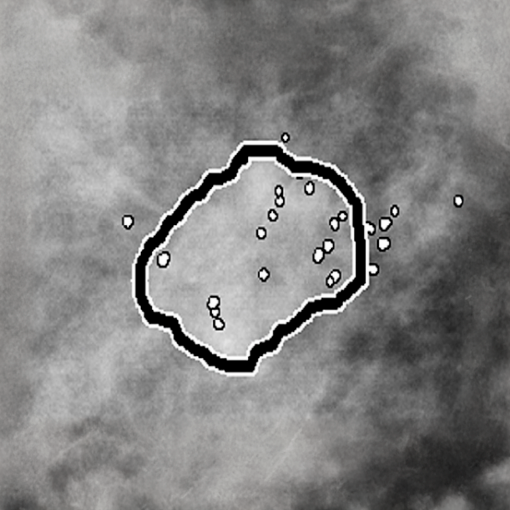

Hologic entiende que hay un cambio constante mamografía y que existe la necesidad de la necesidad de softwares que ayuden en el diagnóstico. El CAD provee detección en imágenes 2D, imagen sintetizada C-View e Intelligent 2D, las cuales provienen del volumen de tomosíntesis. Utilizando sofisticados algoritmos el CAD busca potenciales microcalcificaciones y masas -características asociadas con cáncer. Sobre la imagen se posicionan marcas en las áreas de sospecha para enfocar la atención del radiólogo; el resultado de los algoritmos altamente sensibles resulta sin exceso de falsos-positivos entregando una revisión exhaustiva. Cuando se utiliza sobre imágenes 2D en combinación con Smart Mapping, es posible encontrar la lesión de sospecha sobre el set de cortes de tomosíntesis

En adición a la detección de regiones de interés, los algoritmos del CAD también incorporan tecnología de correlación anatómica, entregando información sobre la mama contralateral y diferentes vistas en la misma mama. También es posible para el operador ajustar la sensibilidad del CAD, o puntos operativos, dependiendo de la práctica diaria; una región va a ser marcada en la medida que el ranking de puntuación caiga sobre la línea del punto operativo. Se pueden seleccionar hasta 3 puntos operativos en imágenes 2D y un punto en imágenes sintetizadas.